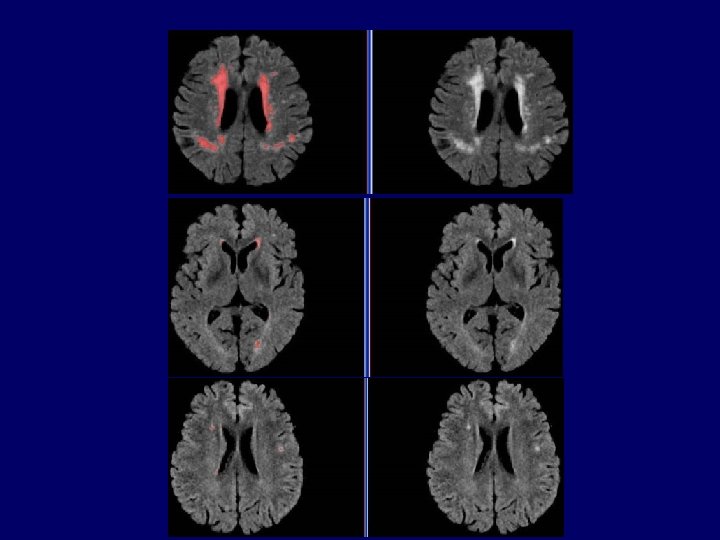

Segmentation of Brain Lesions FLAIR threshold = -1 Manual definition threshold = 0 threshold = 2